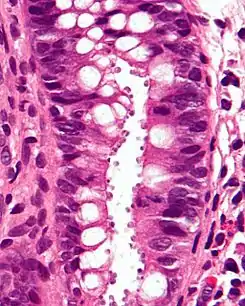

Micrografía que muestra la criptosporidiosis. El Cryptosporidium son los cuerpos pequeños y redondos en la superficie del epitelio. Tinción H&E. Biopsia de colon.